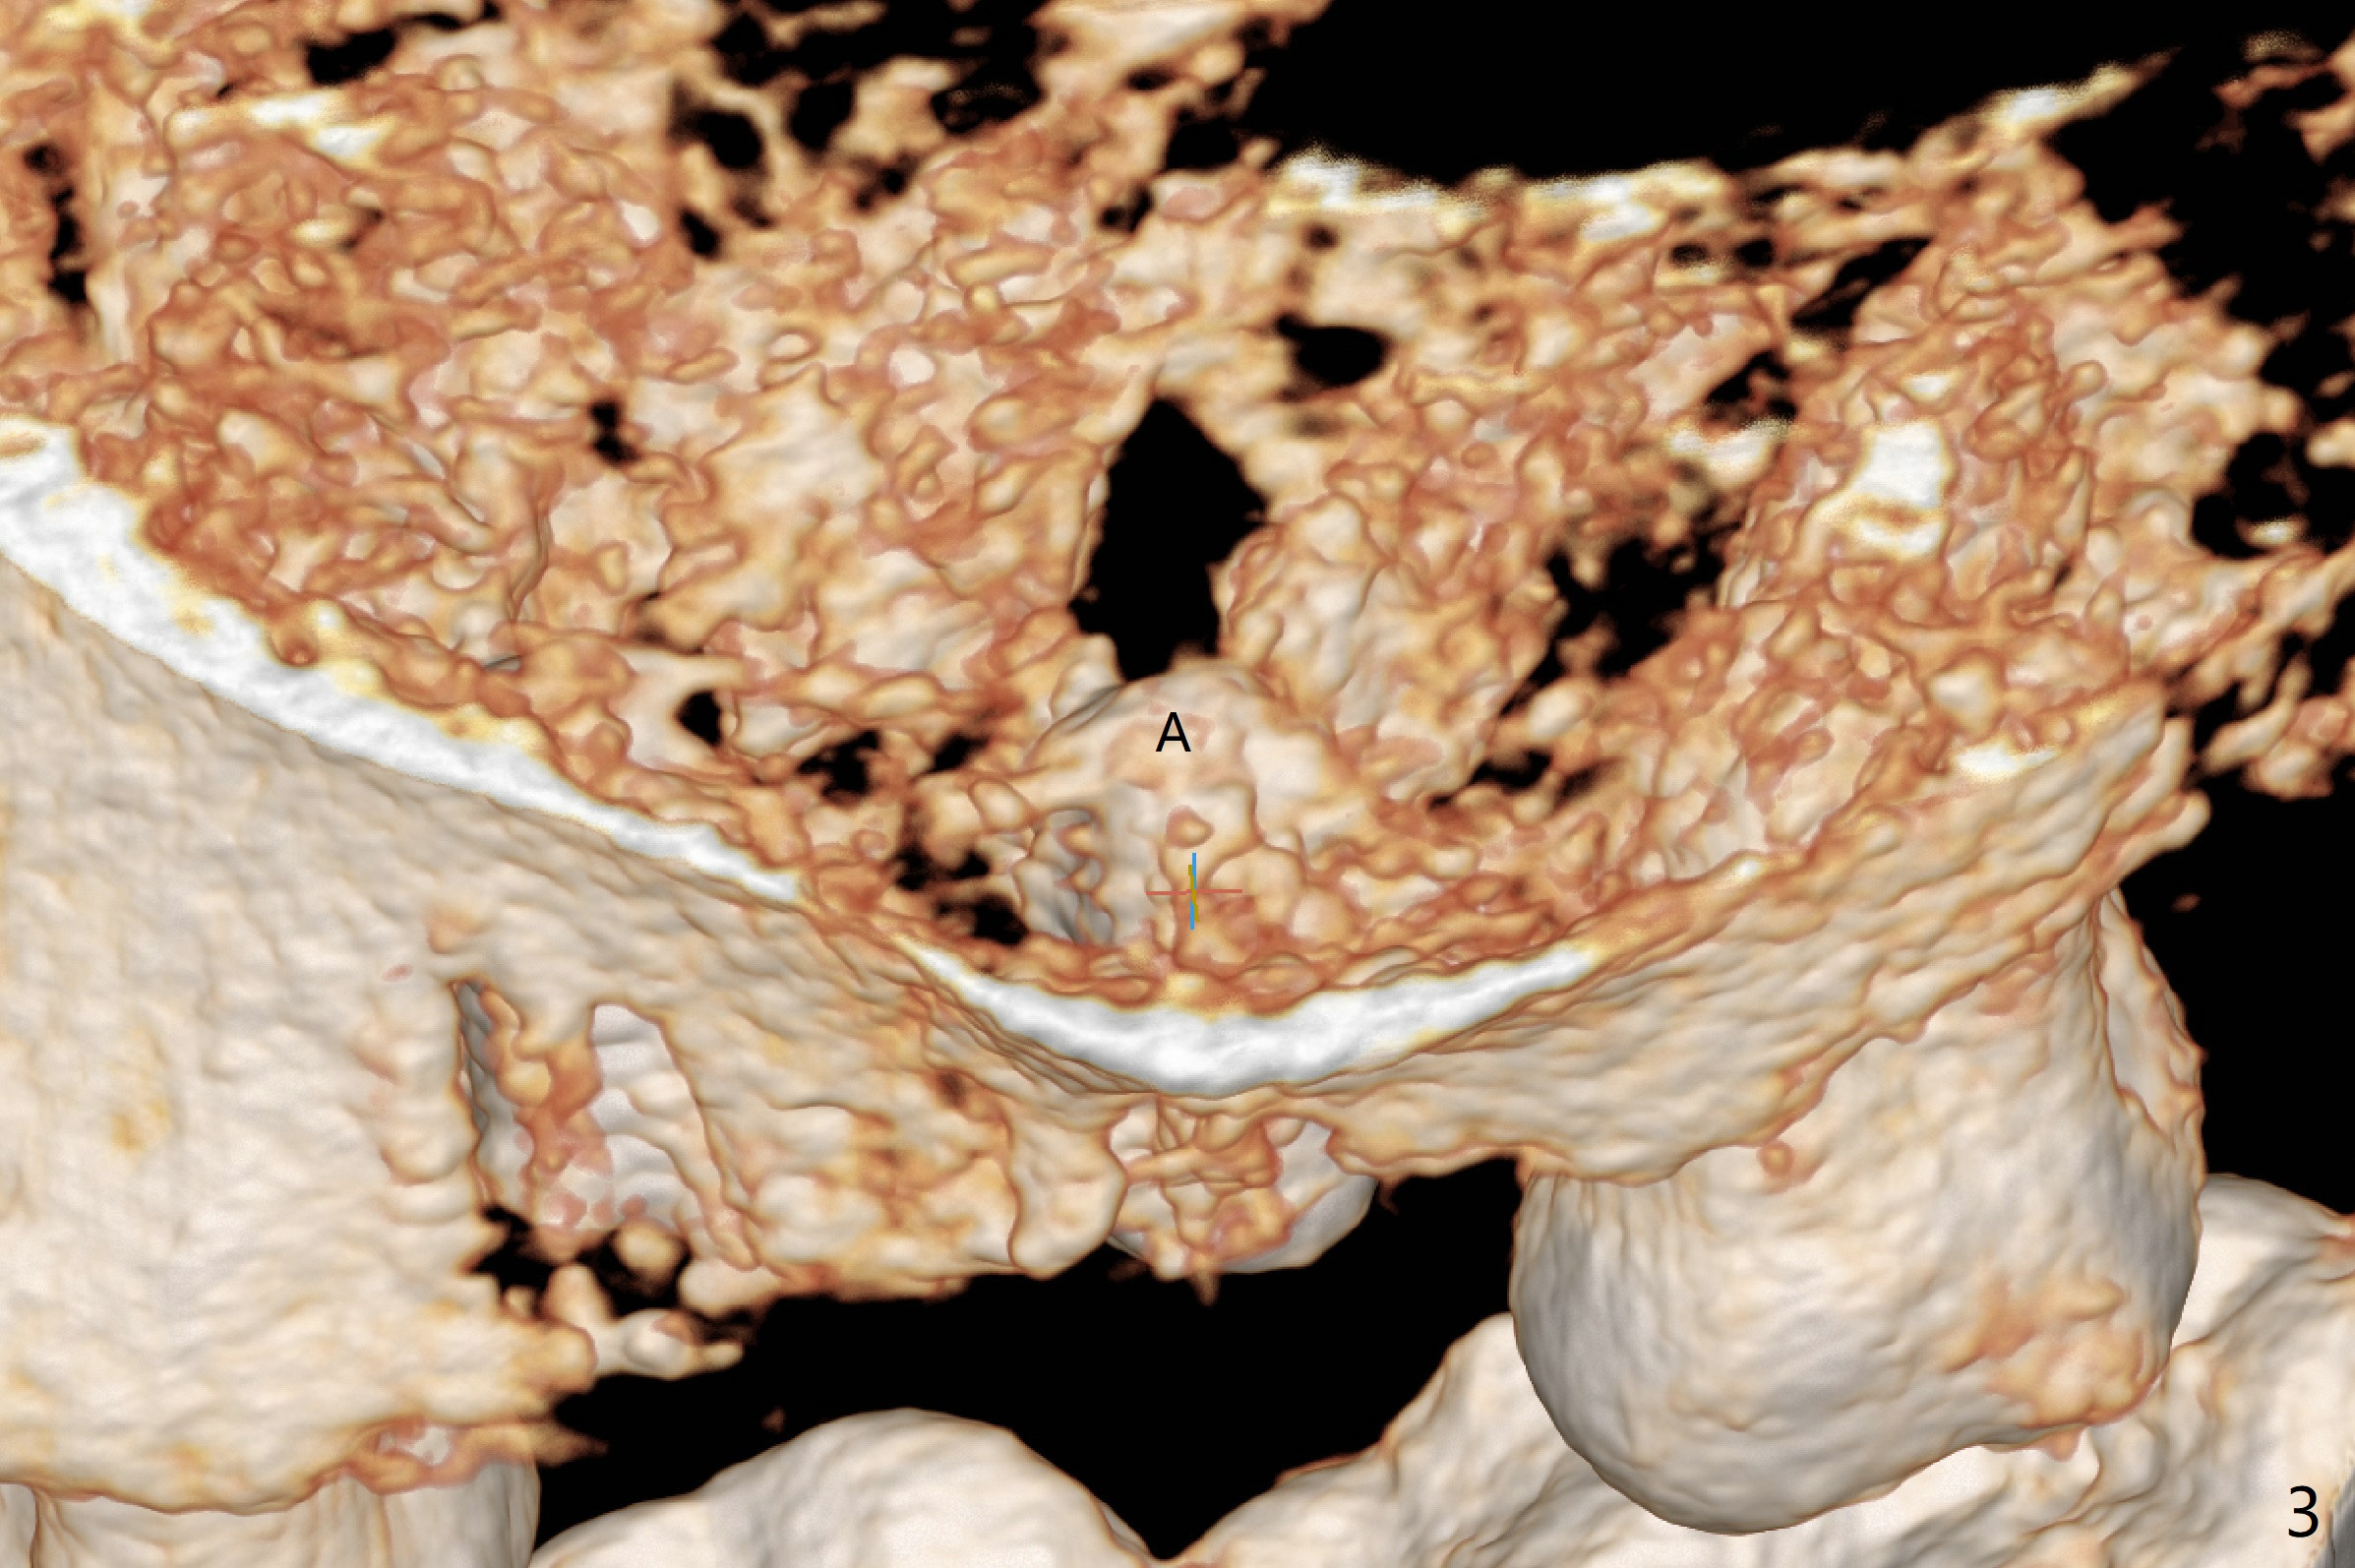

Four and a half months post implant removal, the patient returns for #14 implant placement. To increase bone density, bone expanders are used through the metal sleeve of the previous guide after use of 2.2x7.5 mm drill with 3 O-rings (1 mm shorter than previously designed; Fig.1). The osteotomy continues to form by bone expanders until 2.4/3.7 mm, followed by a 4x10 mm dummy implant (Fig.2-4). Finally a 4.5x7.3 mm implant is placed with ~ 25 Ncm with simultaneous sinus lift (Fig.5). There is no postop nasal hemorrhage. The implant dislodges with the healing abutment 2 months postop. The patient will return for follow up 3 months post 2nd loss. We are going to try again with PRF, UF guided sinus lift kit, sinus expander kit. After implant placement, use the implant at #13 and abutments at #13 and 14 to fabricate splinted provisional to hole the newly placed implant in place. Take preop PA and possible CT. In fact CT and impression are retaken for a new guide.